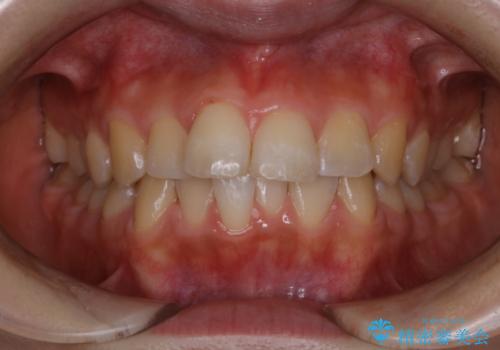

またPMTCを行うことで、ご自身本来の歯の色になり自然な明るさになります。

口元が自然な明るさになることで、より清潔感のある印象になるため結婚式・行事やイベント前などにもPMTCを行うはおすすめです。

- 結婚式があるため、できる限りできれいにクリーニンングしてほしいとのことでした。PMTC60分コースを行いました。